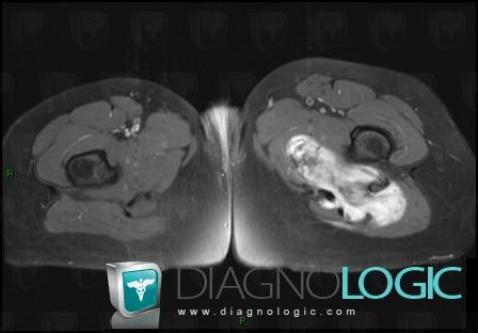

Desmoid tumor, Muscles - Thigh, Other soft tissues/nerves - Thigh, MRI

Here is the specific information in the key image above:

- Diagnosis Desmoid tumor, Location(s) Muscles - Thigh, with gamuts Cystic and cystic-like soft tissue massOther soft tissues/nerves - Thigh, with gamuts Cystic and cystic-like soft tissue mass